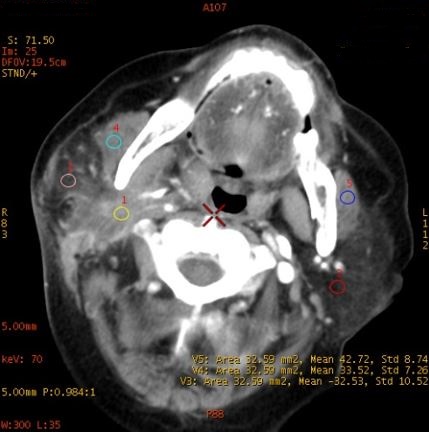

病例资料: 女,72岁,颈部肿胀就诊

CT印象 右侧颈部间隙感染

CNR:64keV 最佳单能对比噪声信号比成像

70keV

ROI 1 颈部间隙感染 ROI 2 正常腮腺内脂肪 ROI 3 受感染侵犯的脂肪间隙 ROI 4-5 双侧咀嚼肌